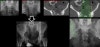

엉치뼈 선의 단절은 골절의 강력한 증거가 됩니다. 절구에 대한 검사에는 여러 개의 가상의 선들이 도움이 됩니다(Iliopectineal line, Ilioischial line, Tear drop line).

절구의 골절은 피질의 모서리를 따라서 주행하며 찾아내서 위에 언급한 여러 개의 선들을 참고합니다.